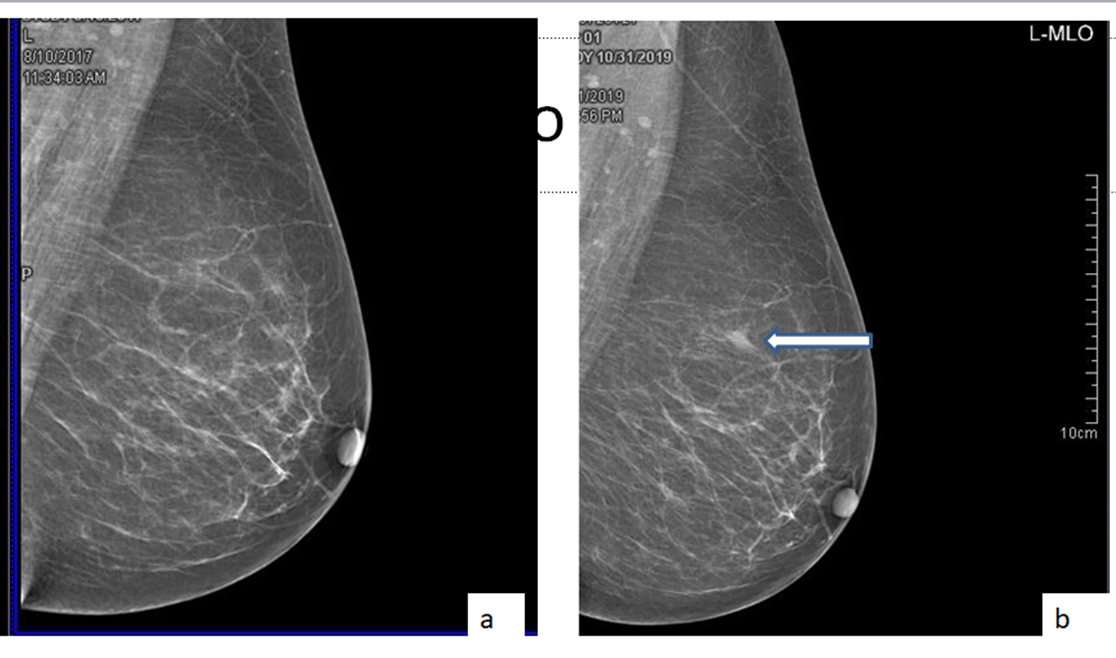

A postmenopausal woman who has previously been treated for contralater...

Read More